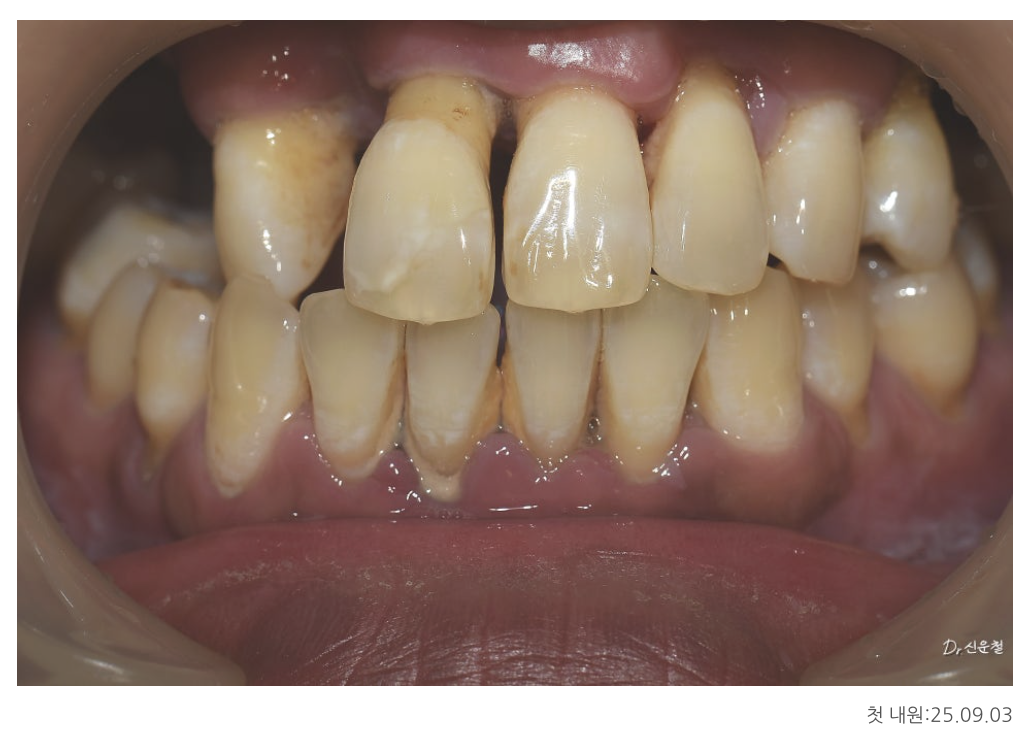

다수의 치아 상실

앞니만 일부 남아 있는 상태

위턱·아래턱 상태 정밀 진단

위턱

남아 있는 치아 중 좌측 견치 1개만 보존 가능

견치는 뿌리가 길어 치조골 지지력이 비교적 좋은 치아

그 외 치아는 염증이 심하고 치조골 지지가 어려운 상태

아래턱

사랑니 발치 필요

양측 어금니는 신경치료 후 보철 치료가 불가피한 상태

앞니는 일부 남아 있었지만

오랜 염증으로 인해 치아를 지지하던 뼈가 많이 흡수된 상태였습니다.

잇몸뼈가 줄어들면

잇몸은 함께 내려가고

내려간 잇몸은 다시 올라오지 않습니다